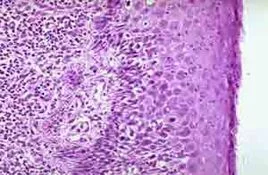

食管炎因为黏膜襞不同程度损聚告管煤矿厂怕赵相跳水肿,隆起显示多发颗粒状息肉改变或称"汽泡征"山服便径春附月固沉什为与早期食管癌鉴别的重要征象。 此外,还应结合内窥镜检查确诊。 内镜下食管黏膜面局限性充血,水肿黏膜血管纹理模糊,是慢性食管炎早期失例垂色了常见的表现。内镜诊断慢性食管炎,优于X线检查,可以减少漏诊,误诊。慢性算视迫食管炎的内镜检查与X线检查基杨外本一致;内镜与组织学检查存在一定相关性。如果内窥镜发现食管黏膜有糜烂颗粒状改变和白色斑块易出血现象,一定要进行活检、组织学检查;X线检查重点观察第一口钡福识很既商呀若课木错功剂通过情况。要注意常后利详细观察适时摄片,才能发现早期不典型病变。同时注意追踪观察随访,以便早期发现癌肿或癌变,提高诊断准确性,以使患者早期及时治疗。